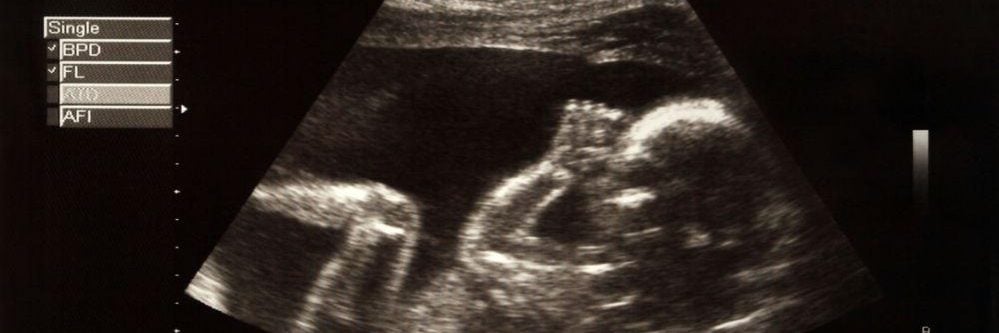

במהלך סקירות טרום לידתיות, הרופא שלך יכול להשתמש בטכנולוגיית אולטרסאונד להצגת תמונות של העובר, כמו גם בגנטיקה מולקולרית, כדי לזהות הפרעות.

בנוסף לאולטראסאונד ברזולוציה גבוהה, הרופא שלך עשוי לבצע בדיקת סיסי שליה (CVS) לצורך בדיקת חלק מהשליה לאיתור הפרעות כרומוזומליות או גנטיות.